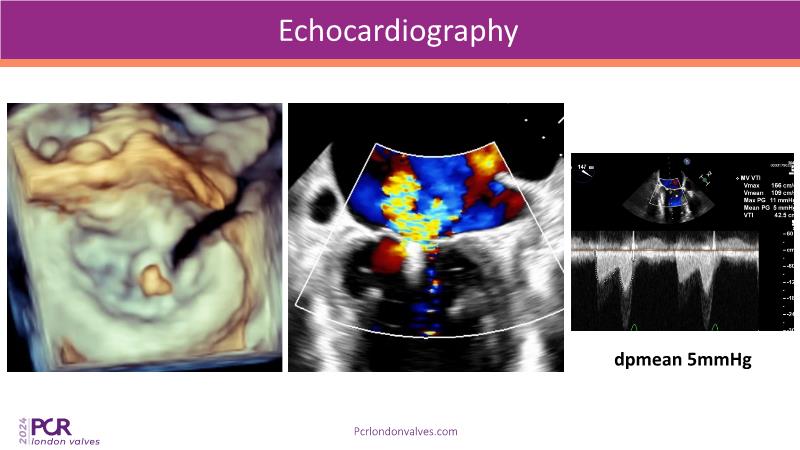

This session examines two compelling cases: a 78-year-old woman with paroxysmal atrial fibrillation, chest trauma, an osteoporotic sternum fracture, and NYHA II exertional dyspnoea, and an 82-year-old man with chronic three-vessel coronary artery disease, bradycardic AF, peripheral arterial disease, spinal stenosis, and chronic kidney disease. Through their study, discover the intricate anatomy of atrioventricular valves, the therapeutic challenges they pose, and the growing significance of transcatheter edge-to-edge repair (TEER) therapies. The discussion also highlights the value of multidisciplinary strategies in managing complex valve diseases effectively.